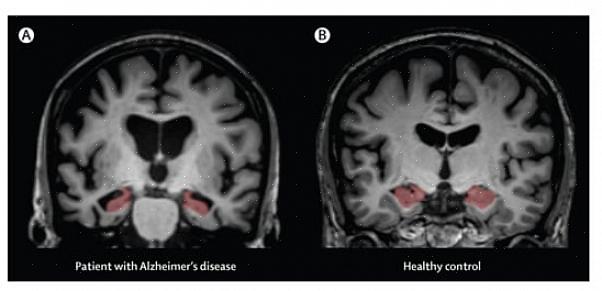

כפי שאמרנו קודם, מבחן זה פותח ויושם לראשונה בשנת 1953. היא ביקשה להעריך אפרקסיה בונה (שכיחה בדמנציה) וגם לזהות את היקף הנגעים של הקורטקס הפריאטלי.

לאט לאט, כאשר אנשים התחילו לראות כמה זה יעיל, זה הפך לכלי חיוני באבחון הידרדרות קוגניטיבית. קשור במיוחד לשלבים הראשונים של מחלת האלצהיימר.